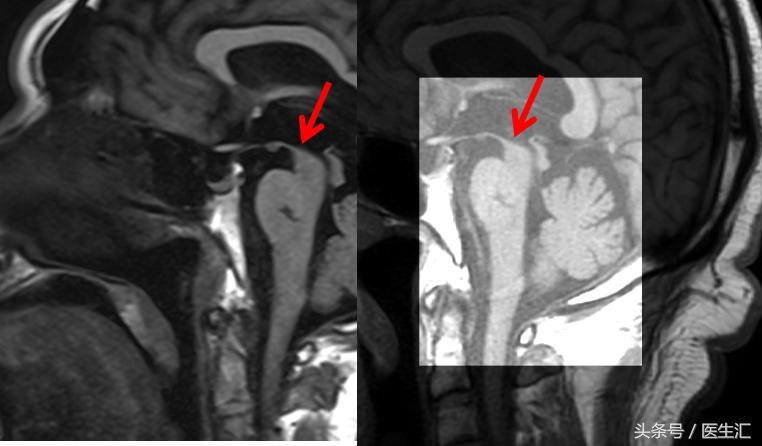

影像检查

进行性核上性麻痹-帕金森型